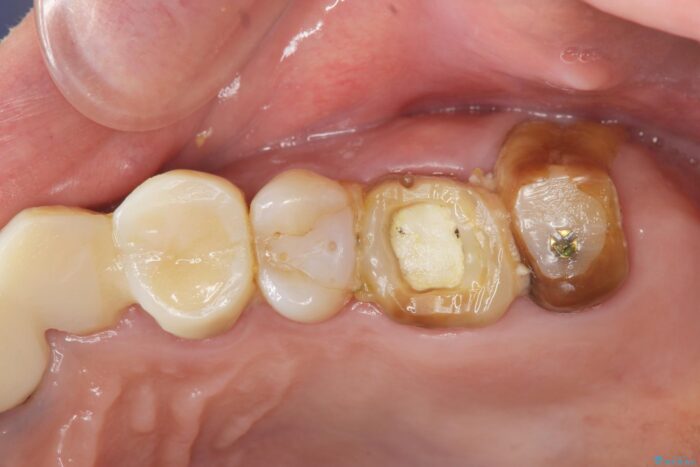

他院での治療の途中で通院をやめてしまい、当院で治療の続きを希望された患者様です。

クラウンが装着されておらず、つぎはぎだらけの処置歯を、精度の高いセラミッククラウンを用いて歯ブラシのしやすい環境整備を行っていきます。